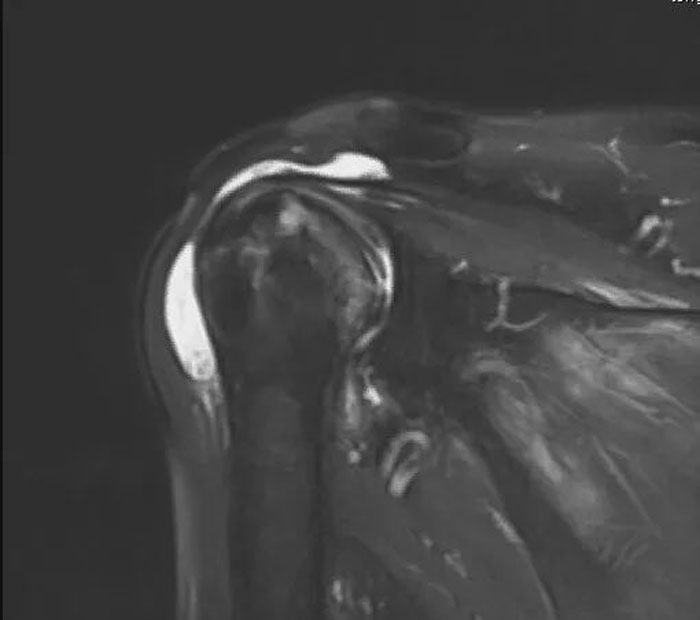

肩關(guān)節(jié)是人體所有關(guān)節(jié)中活動量最大、最靈活的一個關(guān)節(jié),任何損傷都會讓患者“飽受肩熬”。本例患者賀大爺肩關(guān)節(jié)疼痛數(shù)月,夜間疼痛嚴(yán)重,影響睡眠,肩關(guān)節(jié)活動明顯受限,行磁共振檢查提示肱骨頭壞死并肩袖損傷。康立新主任醫(yī)師在考慮患者病情、影像學(xué)檢查、風(fēng)險評估、術(shù)后獲益以及患者和家屬意愿的基礎(chǔ)上,建議患者行反式人工全肩關(guān)節(jié)置換術(shù),重建患者肩關(guān)節(jié)。

術(shù)前